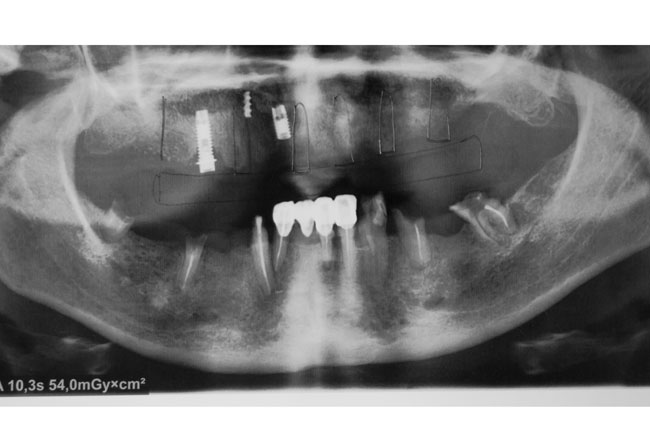

In 08.01.2014 the patient were made surgery. In 1.6; 1.3; 1.2; 2.1; 2.3; 2.5 were set Alpha Dent implants 10-13-16 mm length and a diameter of 3.75 – 4.2 mm. Implant 1.2 was installed by passing method between the remaining portions of the previously installed (1999) implants. All implants Alpha Dent were established in “bloodless” way by using tissue punch, without sutures. The postoperative period was uneventful. For rehabilitation period of patient P. made a temporary removable denture in upper jaw was made, which she used for the entire treatment period (from surgery to manufacturing a permanent prosthesis). There was a 5 months period of using a temporary removable prosthesis.

In 02.05.2014 the second stage of rehabilitation was made. Revealed endosseous part 6 Alpha Dent implants in the upper jaw were opened, gums conditioners installed and restored abutment of 15-years old implant in 1.5 using titanium cap. The success rate of implantation in the rehabilitation of patient P. with edentulous maxilla reached 100% (see Fig. 4, 5).